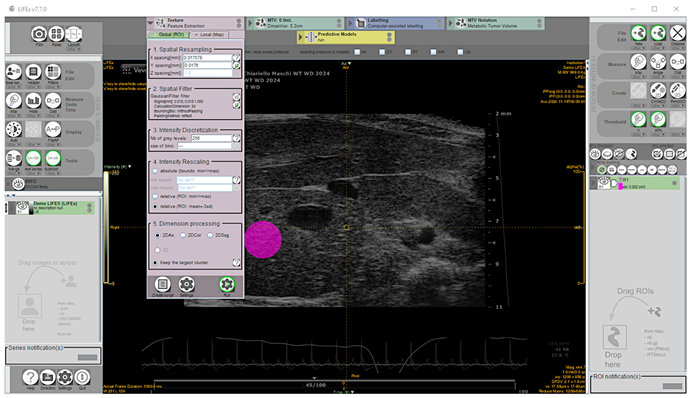

39]. A total of 135 images, including 87 from mice diagnosed for hepatic steatosis of any degree on histology, and 48 from mice for which the disease was excluded, were analyzed offline. The texture feature extraction from HFUS images was performed using the open-source application LIFEx v7.7.0 (LITO, Curie, Iserm, CNRS, Paris-Sud, University Paris Saclay, Orsay. Download available from 18 November 2024) [

40]. Proprietary file formats were converted to the Digital Imaging and Communications in Medicine (DICOM) format and stored in a digital image archive. The workflow of the proposed CAD scheme consisted of the following steps: (1) image selection; (2) liver segmentation; (3) image pre-processing; (4) feature extraction; (5) feature selection. Briefly, a complete set of HFUS images in DICOM format was loaded into the Graphical User Interface (GUI), then one HFUS image was selected for each scanned liver lobe at a defined time point, representing the best frame in the cine loop (according to the criteria described above). To perform segmentation, a single-stack image series must be saved from RGB color recorded layers as active reference using the “save series” tool (format: DICOM; size: 2D) and the chosen frame loaded. To ensure consistency and reliable statistics, a 100-voxel circular region of interest (ROI) was manually placed on the liver parenchyma in the focal area as close as possible to the image center to minimize echo distortion artifacts, avoiding vascular or biliary system structures. [

41]. Subsequently, a low pass 2D Gaussian filter was applied to the ROI images for speckle noise reduction and feature repeatability improvement (kernel: X, Y = 0.018 mm; padding method: reflect, on the exact bounding box of the activated ROI without additional padding) [

14,

42,

43]. Before texture analysis, signal intensity in the ROI was corrected by the mean and three standard deviations to minimize overall grayscale variation between images and scanners [

41]. Then, texture-related features were computed (spatial resampling: x-spacing = 0.017578 mm, y-spacing = 0.0176 mm; intensity discretization ROI drawn: N. Gray Level = 256; bin size = 0.30; intensity rescaling: relative) [

43,

44] (

Figure 2).

Overall, CAD scheme computed image features and created three feature pools for each experimental group, based on observational ages (8, 16, 24 weeks). Each CAD analysis on HFUS, including total liver lobes from an animal to ensure a representative sampling of the liver parenchyma, took no more than 15 min.